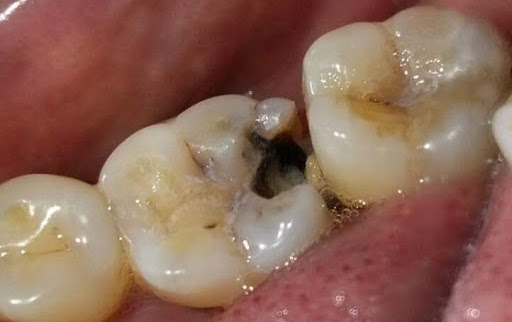

L'odontoiatria conservativa si occupa in sostanza della cura dei denti colpiti da carie.

Questo comprende sia le procedure per l'eliminazione della carie che quelle relative alla chiusura delle

cavità provocate dall'eliminazione della dentina cariata e dello smalto, tramite l'utilizzo di appositi

materiali.

E' detta conservativa in quanto si tende a conservare il più possibile le strutture dentali residue colpiti dalla carie. Si cerca cioè di avere un approccio di minima invasività.

Il materiale di restauro viene legato direttamente al tessuto sano.

In passato venivano usate amalgame d'argento, ma ora sono state totalmente abbandonate a favore dei

Compositi.

Questo non solo per il loro aspetto antiestetico rispetto ai materiali moderni, ma anche perchè le vecchie

amalgame vengono ora ritenute dannose a causa della presenza di metalli pesanti tra i quali il mercurio.

I materiali compositi attuali invece, oltre ai vantaggi di maggior resistenza e durata, hanno la caratteristica di essere molto simili allo smalto del dente, creando un effetto di ricostruzione perfetta e del tutto simile ai denti sani.